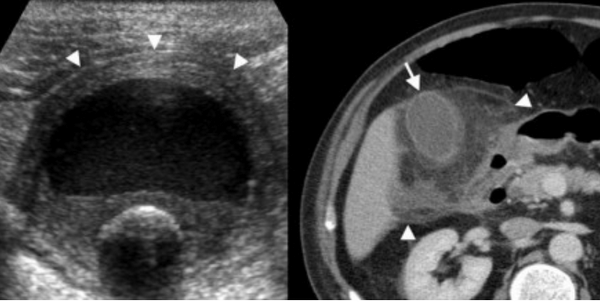

Слева — УЗИ — желчного пузыря у 59 летней женщины с острым холециститом. Субсерозный отек так, как гипоэхогенное утолщение между гиперэхогенными слоями (мышечным и слизистым). Справа — КТ брюшной полости с контрастным усилением. Также визуализируется субсерозный отек так, как наружный слой гиподенсный.

Острый калькулезный холецистит. После контрастного усиления визуализируется растянутый желчный пузырь (белые наконечники) со слегка утолщенной стенкой. Визуализируется камень в шейки желчного пузыря (белая стрелка).

Сверху изображения пациента 62 лет с калькулезным холециститом. На УЗИ визуализируется стенки желчного пузыря растянутые, с субсерозным отеком (указано белыми стрелками) и в просвете желчного пузыря камень и взвесь. На КТ визуализируется переход воспалительного процесса с желчного пузыря на соседние ткани (перихолецистит).